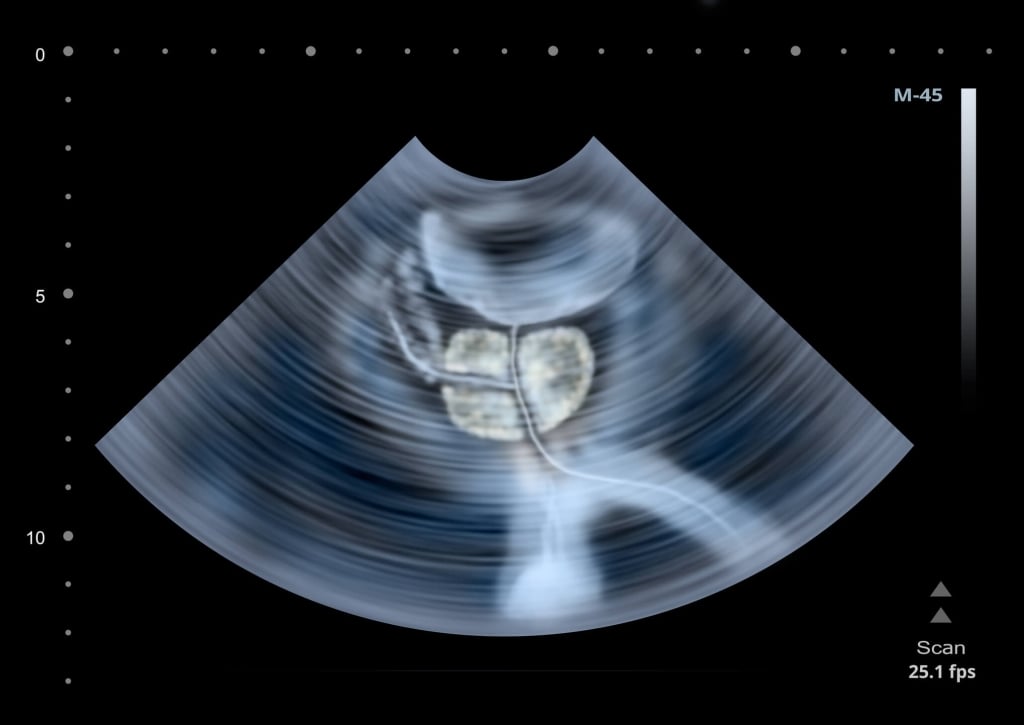

L’aumento volumetrico (appunto, l’ipertrofia prostatica benigna) è un fenomeno legato all’età, e si verifica, più o meno, in tutti gli uomini a partire dai 35-40 anni. Interessa l’area più interna della prostata, quella cioè a contatto con il collo della vescica ed è quindi responsabile dei sintomi urinari (frequenza, urgenza e difficoltà a urinare) che si manifestano a partire dai 50 anni.

Il tumore invece si sviluppa quasi sempre nella porzione periferica della ghiandola, non è in contatto diretto con la vescica e quindi, specie nella fase iniziale, non da segni di sé e non da sintomi.